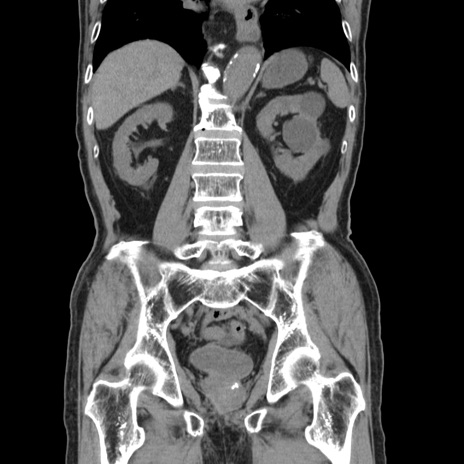

症例24(冠状断像)

【症例】80歳代男性

【主訴】左側腹部痛、嘔吐

【現病歴】本日早朝より左腹部に痛みあり。昼頃嘔吐認めたため、救急要請。

【既往歴】直腸癌(Mile手術)、胆摘

【身体所見】意識清明、BT 35.9℃、BP 221/93mmHg、SpO2 97%(RA) 、腹部:左ストーマ周囲に限局性の腹部膨隆あり。 膨隆部自発痛・圧痛あり・軟。

【データ】WBC 7700、CRP 0.09